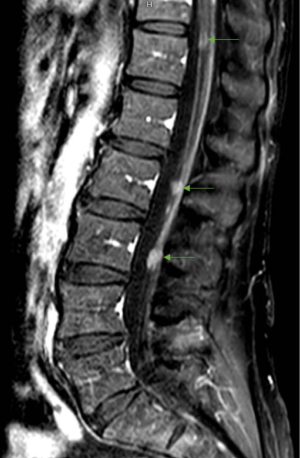

Patients may present with focal or diffuse disease on contrast-enhanced MR imaging of the brain and/or spine. There are variations in the radiographic appearance of LMD including linear/curvilinear enhancement, cranial nerve/nerve root enhancement, or nodular enhancement (27). Intracranial LMD tends to present along the cerebral convexities, cerebellar folia, basal cisterns and ventricular ependyma (Figure 1). Within the spine, all levels of the spinal cord are at risk, however LMD is commonly observed as enhancement and/or nodularity in the cauda equina (Figure 2).

Establishing a clinical diagnosis of LMD based on history and physical exam alone is generally not possible given the variability and non-specificity of signs and symptoms. Therefore, imaging and CSF cytology remain the cornerstones of a complete work-up for LMD. Gadolinium-enhanced MRI is the best imaging modality for detecting LMD and should include both the brain and complete spine given that the entire neuraxis is at risk (1,11). The sensitivity and specificity of contrast-enhanced MRI in diagnosing LMD ranges from 70–85% and 75–90%, respectively (2,22,23). LMD may present as enhancement of the brain surface, cerebellar foliae, cerebral sulci, cranial nerves, and spinal nerve roots (24-26). Pathological enhancement may appear as nodular, linear, or curvilinear, and is described as either focal or diffuse intensification (27). Intradural extramedullary enhancing nodules in the subarachnoid space are common in disease involving the cauda equina and can be difficult to quantify given their small size and propensity to be adjoined by linear enhancement (11). Subependymal deposits and communicating hydrocephalus can also occur (7). Imaging should be completed prior to neurological procedures such as lumbar punctures, as they may cause inflammation or lower the ICP leading to extraneous enhancement and potential false positives (1,2). Conversely, a negative MRI does not exclude the presence of LMD, as 20–30% of patients with LMD have a normal MRI (28).